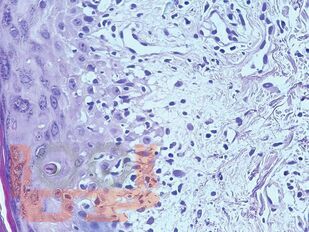

Атлас содержит авторские гистологические иллюстрации различных ревматических заболеваний, включая ревматоидный артрит, системную красную волчанку, системную склеродермию, а также редкие патологии: склеромикседему, IgG4‑ассоциированное заболевание, панникулиты, аутовоспалительный синдром, ассоциированный с адъювантами (ASIA‑синдром). Широко представлены системные васкулиты (болезнь Такаясу, гигантоклеточный артериит, узелковый полиартериит, гранулематоз с полиангиитом, эозинофильный гранулематоз с полиангиитом и др.). Гистологические препараты сопровождаются фотографиями пациентов.